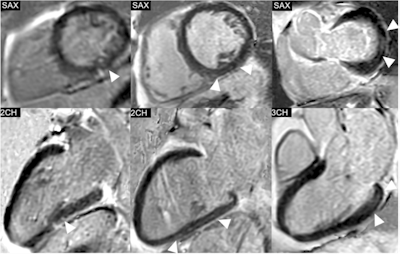

Phase-sensitive inversion recovery (PSIR) images of the left ventricle (LV) in short-axis (SAX) views and the corresponding 2-chamber (2CH) or 3-chamber (3CH) views, showing the distribution of non-ischemic late gadolinium enhancement (LGE) in three exemplary study patients. Left: Punctiform subepicardial LGE of the midventricular inferior LV in a 63-year-old male patient with cirrhosis due to primary sclerosing cholangitis (MELD score: 18 points, Child-Pugh class B). Middle: Linear mid-myocardial LGE of the inferior LV in a 54-year-old male liver cirrhosis patient with chronic Hepatitis C virus infection (MELD score: 15 points, Child-Pugh class B). Right: Linear mid-myocardial LGE of the lateral basal LV in a 57-year-old male liver cirrhosis patient with chronic Hepatitis C virus infection (MELD score: 6 points, Child-Pugh class B).